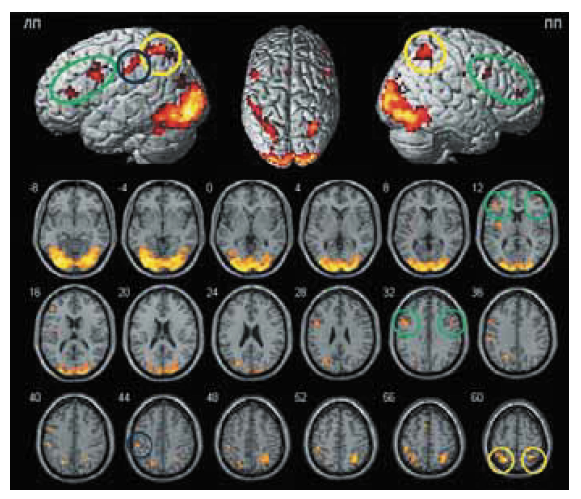

Активация алиментарных зон головного мозга при помощи фМРТ достигается путем предъявления различных стимулов – зрительных, обонятельных или вкусовых [25]. Исследование, как правило, проводится натощак. Одной из наиболее простых в техническом плане и воспроизводимой методикой является предъявление изображений преимущественно высококалорийной пищи, чередующихся с изображениями нейтральных пейзажей [23]. Получаемая в результате активация отражает все звенья описанной выше регуляторной системы пищевого поведения с возможностью их оценки: обширная активация зрительной коры (рис. 1) как следствие выбранного сенсорного входа информации и участия ее в регуляции пищевого поведения и распознании потенциальной пищи, особенно в условиях отсутствия запаха и вкуса; активация элементов интегративного звена – таламуса, верхних теменных долек (7 ПБ) – зон, включенных в дальнейшую обработку информации, поступающей от затылочных долей (зрительной коры) и передачу ее во фронтальную кору [26]. И наконец, активация орбитофронтальной, префронтальной коры, передних отделов поясной извилины, островковой коры и гиппокампов – областей, формирующих пищевое поведение в ответ на поступившие сигналы. С точки зрения нейровизуализации особый интерес представляет ДЛПФК – 9, 46 ПБ. Она получает сенсорную информацию как о самом организме, так и об окружающей среде, а также эмоциональную и когнитивную информацию от лимбической системы, и тесно связана с зонами, ответственными за планирование движения и его выполнение. Поэтому эта область идеально подходит для трансляции всей имеющейся информации о гомеостазе и окружающей среде в адаптивные поведенческие ответы, т.е. принятие решений и проблем выбора [27]. В литературе описано различное изменение объема активации (как уменьшение, так и увеличение) ДЛПФК в левом и/или правом полушариях у пациентов с ожирением [18, 25].

Рис. 1. Зоны активации для группы здоровых добровольцев (групповой анализ) при выполнении парадигмы, наложенные на объемное изображение головного мозга (вверху) и срезы в аксиальной проекции (внизу). ПП – правое полушарие большого мозга, ЛП – левое полушарие. Зеленым цветом обозначена ДЛПФК (9 и 46 ПБ), желтым – верхняя теменная долька (7 ПБ), синим – нижняя теменная долька (40 ПБ). Т>6,32, pFWEcorr <0,05.

2. Рис. 1. Зоны активации для группы здоровых добровольцев (групповой анализ) при выполнении парадигмы, наложенные на объемное изображение головного мозга (вверху) и срезы в аксиальной проекции (внизу). ПП – правое полушарие большого мозга, ЛП – левое полушарие. Зеленым цветом обозначена ДЛПФК (9 и 46 ПБ), желтым – верхняя теменная долька (7 ПБ), синим – нижняя теменная долька (40 ПБ). Т>6,32, pFWEcorr <0,05. | |